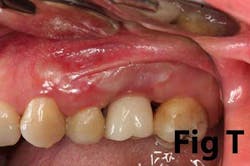

Case No. 1